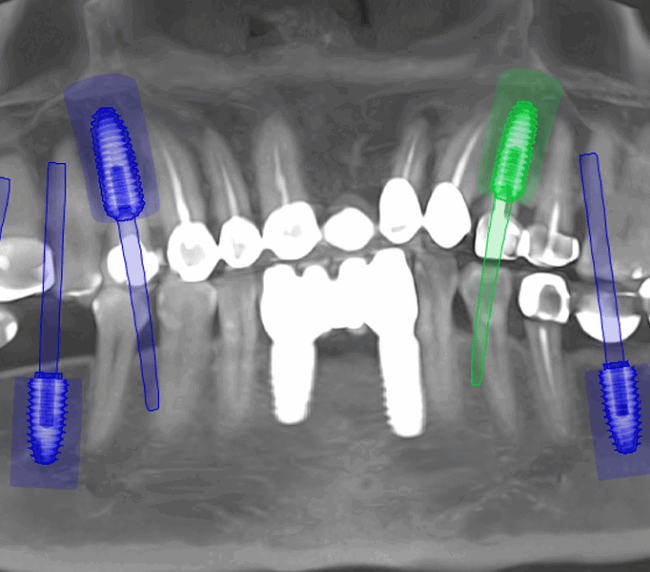

Tomografii (CBCT)

Caz 1

Caz 2

Reabilitarea complexă în stomatologie presupune refacerea completă a sistemului dentoalveolar, atât din punct de vedere funcțional, cât și estetic. Procesul începe cu o examinare detaliată a cavității bucale, interpretarea investigațiilor imagistice (CBCT), evaluarea musculaturii, articulațiilor temporomandibulare și a parametrilor estetici.